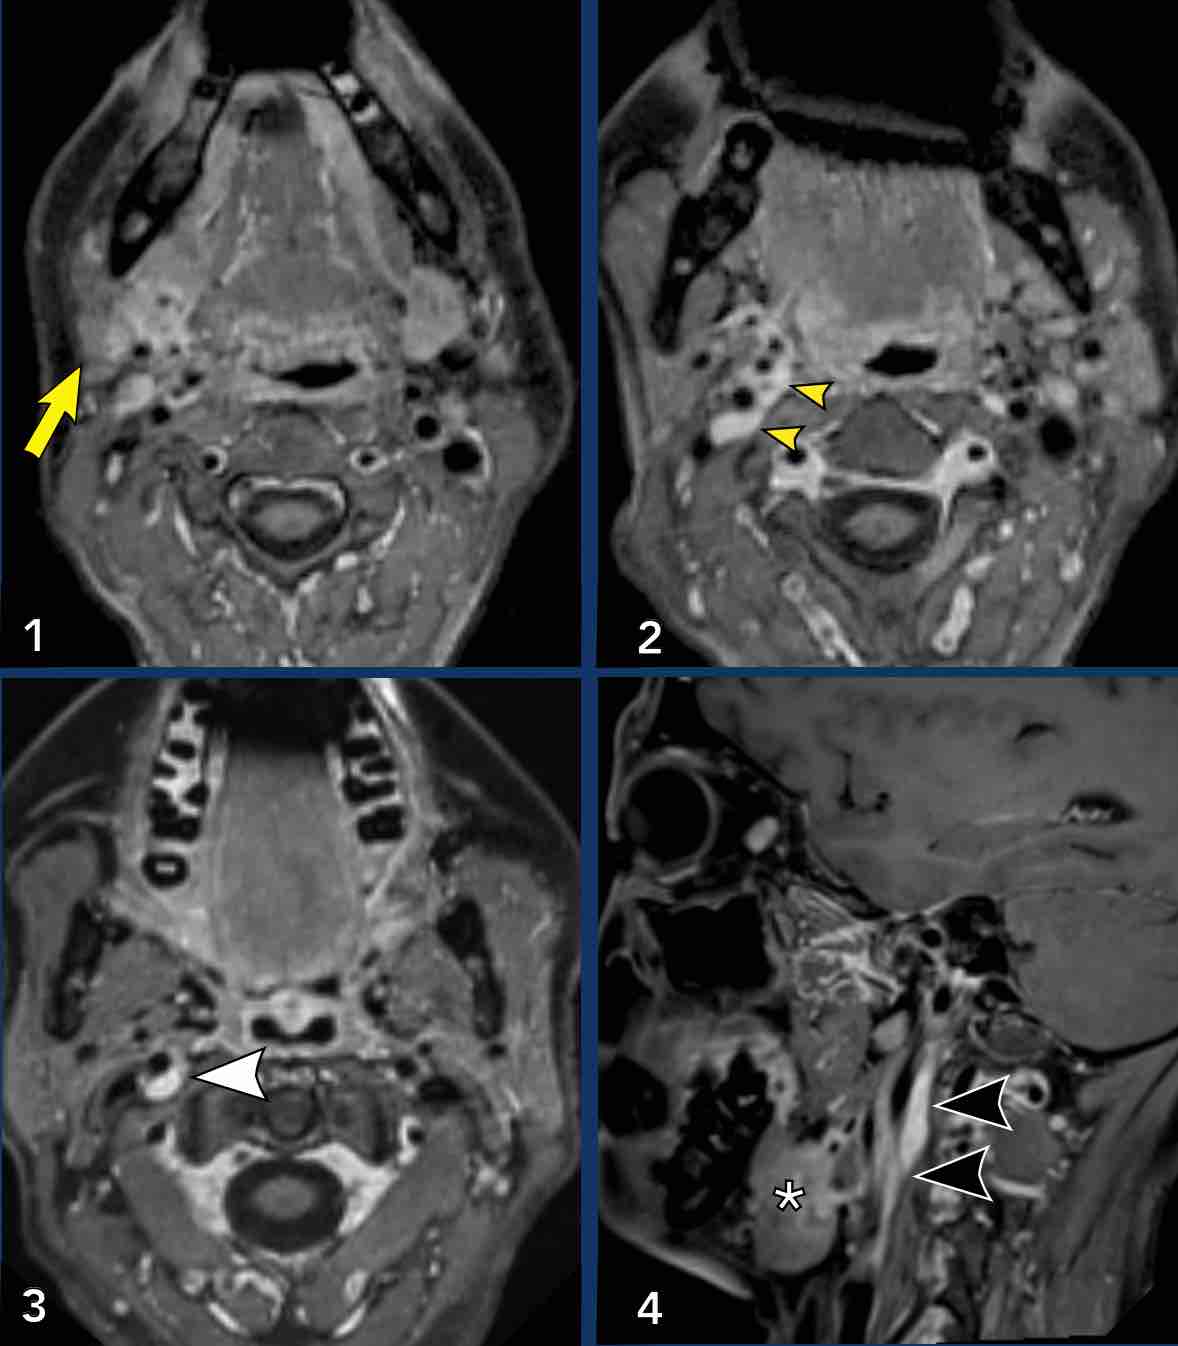

Carotid artery

Ca bệnh

Những

hình ảnh này của một bệnh nhân có khối sưng ở cổ trong vài năm.

Các nghiên cứu hình ảnh học chuyên sâu đã được thực hiện, nhưng tất cả các kết quả đều âm tính.

Bệnh nhân

hiện xuất hiện hội chứng Horner bên phải.

Study the images.

What are the findings?

Images

- Khi bạn so sánh tuyến dưới hàm phải và trái (hình 1), bạn

sẽ nhận thấy một tổn thương khối ngấm thuốc ở bên phải (mũi tên trên hình cuộn). - Sự tăng quang có thể được theo dõi trên hình 2 và 3 dọc theo động mạch cảnh trong và động mạch cảnh ngoài

- Điều này cũng có thể được nhận thấy trên hình ảnh mặt phẳng đứng dọc, nơi tuyến phì đại được nhìn thấy (*) và các vệt tăng quang dọc theo động mạch cảnh trong (đầu mũi tên).

Hình ảnh

Bảy tháng sau, khối u bao quanh động mạch cảnh trong (ICA) và động mạch cảnh ngoài (ECA) đã to hơn.

Kết luận

Đây là ung thư biểu mô tuyến dạng nang với sự lan rộng khối u theo đường thần kinh.